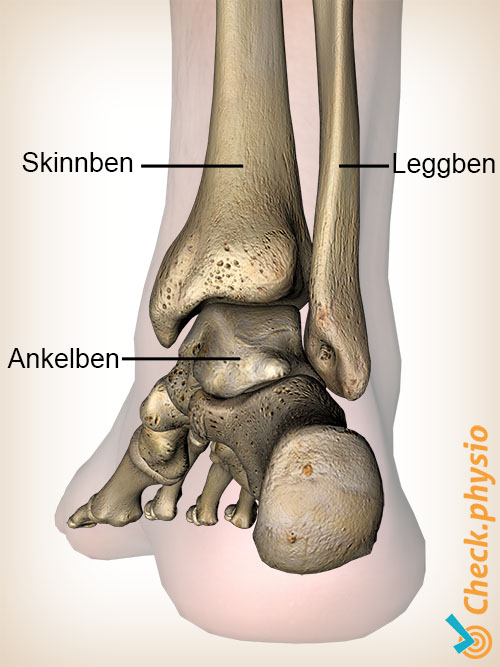

Ankelen består av leggbenet (tibia), leggbenet på utsiden (fibula) og rullebenet (talus). De nedre endene av tibia og fibula danner sammen ankelgaffelen. Rullebenet er omsluttet av disse to beinene. Denne helheten kalles det øvre ankelleddet.